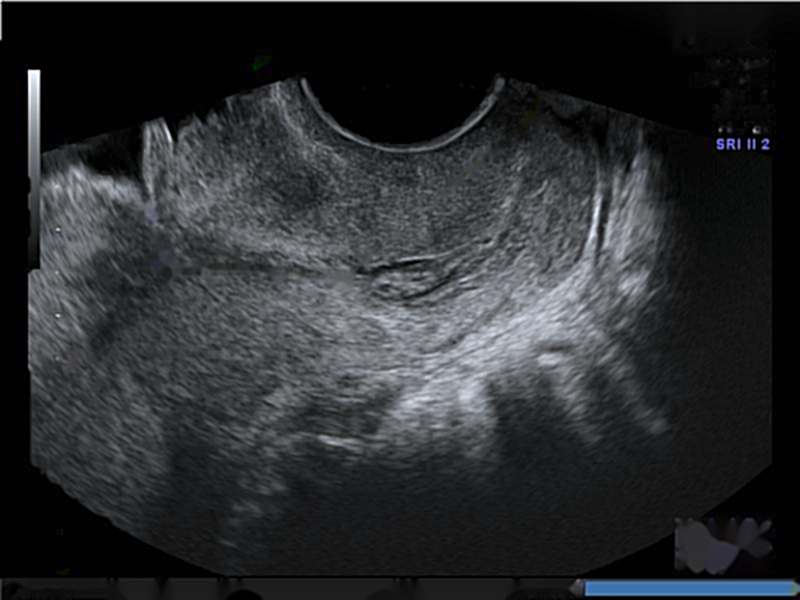

3.3 Grad-CAM

It was found by Baños et al. [14] that information extracted from the region along the length of the anterior cervical stroma is relevant to control vs preterm classification. In addition, Pachtman et al. [15] proved that the region along the length of the anterior cervical stroma and the analysis of its relative organization of cervical collagen fibers may have the capacity to identify preterm birth. To the contrary, Grad-CAM shows the preterm class is classified based on the lower segment of the cervix, close to the ectocervix. We can note that during classification, the neural network focuses on the heterogeneity of the density of tissues around the cervix. For the control class, our model is focusing on the top part of the largest homogeneous region in middle part of anterior cervical lip, which is the part of the cervix closest to the transducer. Examples of Grad-CAM results can be seen in Figure 5 for the preterm and control class.